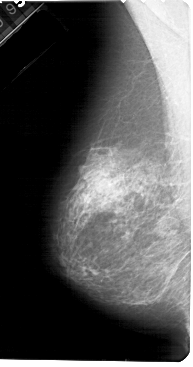

A_1491_1.RIGHT_MLO

A_1491_1.RIGHT_CC

RIGHT_CC LINES 5296 PIXELS_PER_LINE 2536 BITS_PER_PIXEL 12 RESOLUTION 43.5 OVERLAY

RIGHT_MLO LINES 5491 PIXELS_PER_LINE 2836 BITS_PER_PIXEL 12 RESOLUTION 43.5 OVERLAY

FILE: A_1491_1.RIGHT_MLO.OVERLAY

TOTAL_ABNORMALITIES 1

ABNORMALITY 1

LESION_TYPE MASS SHAPE OVAL MARGINS ILL_DEFINED

ASSESSMENT 4

SUBTLETY 1

PATHOLOGY BENIGN

TOTAL_OUTLINES 1

BOUNDARY

FILE: A_1491_1.RIGHT_CC.OVERLAY